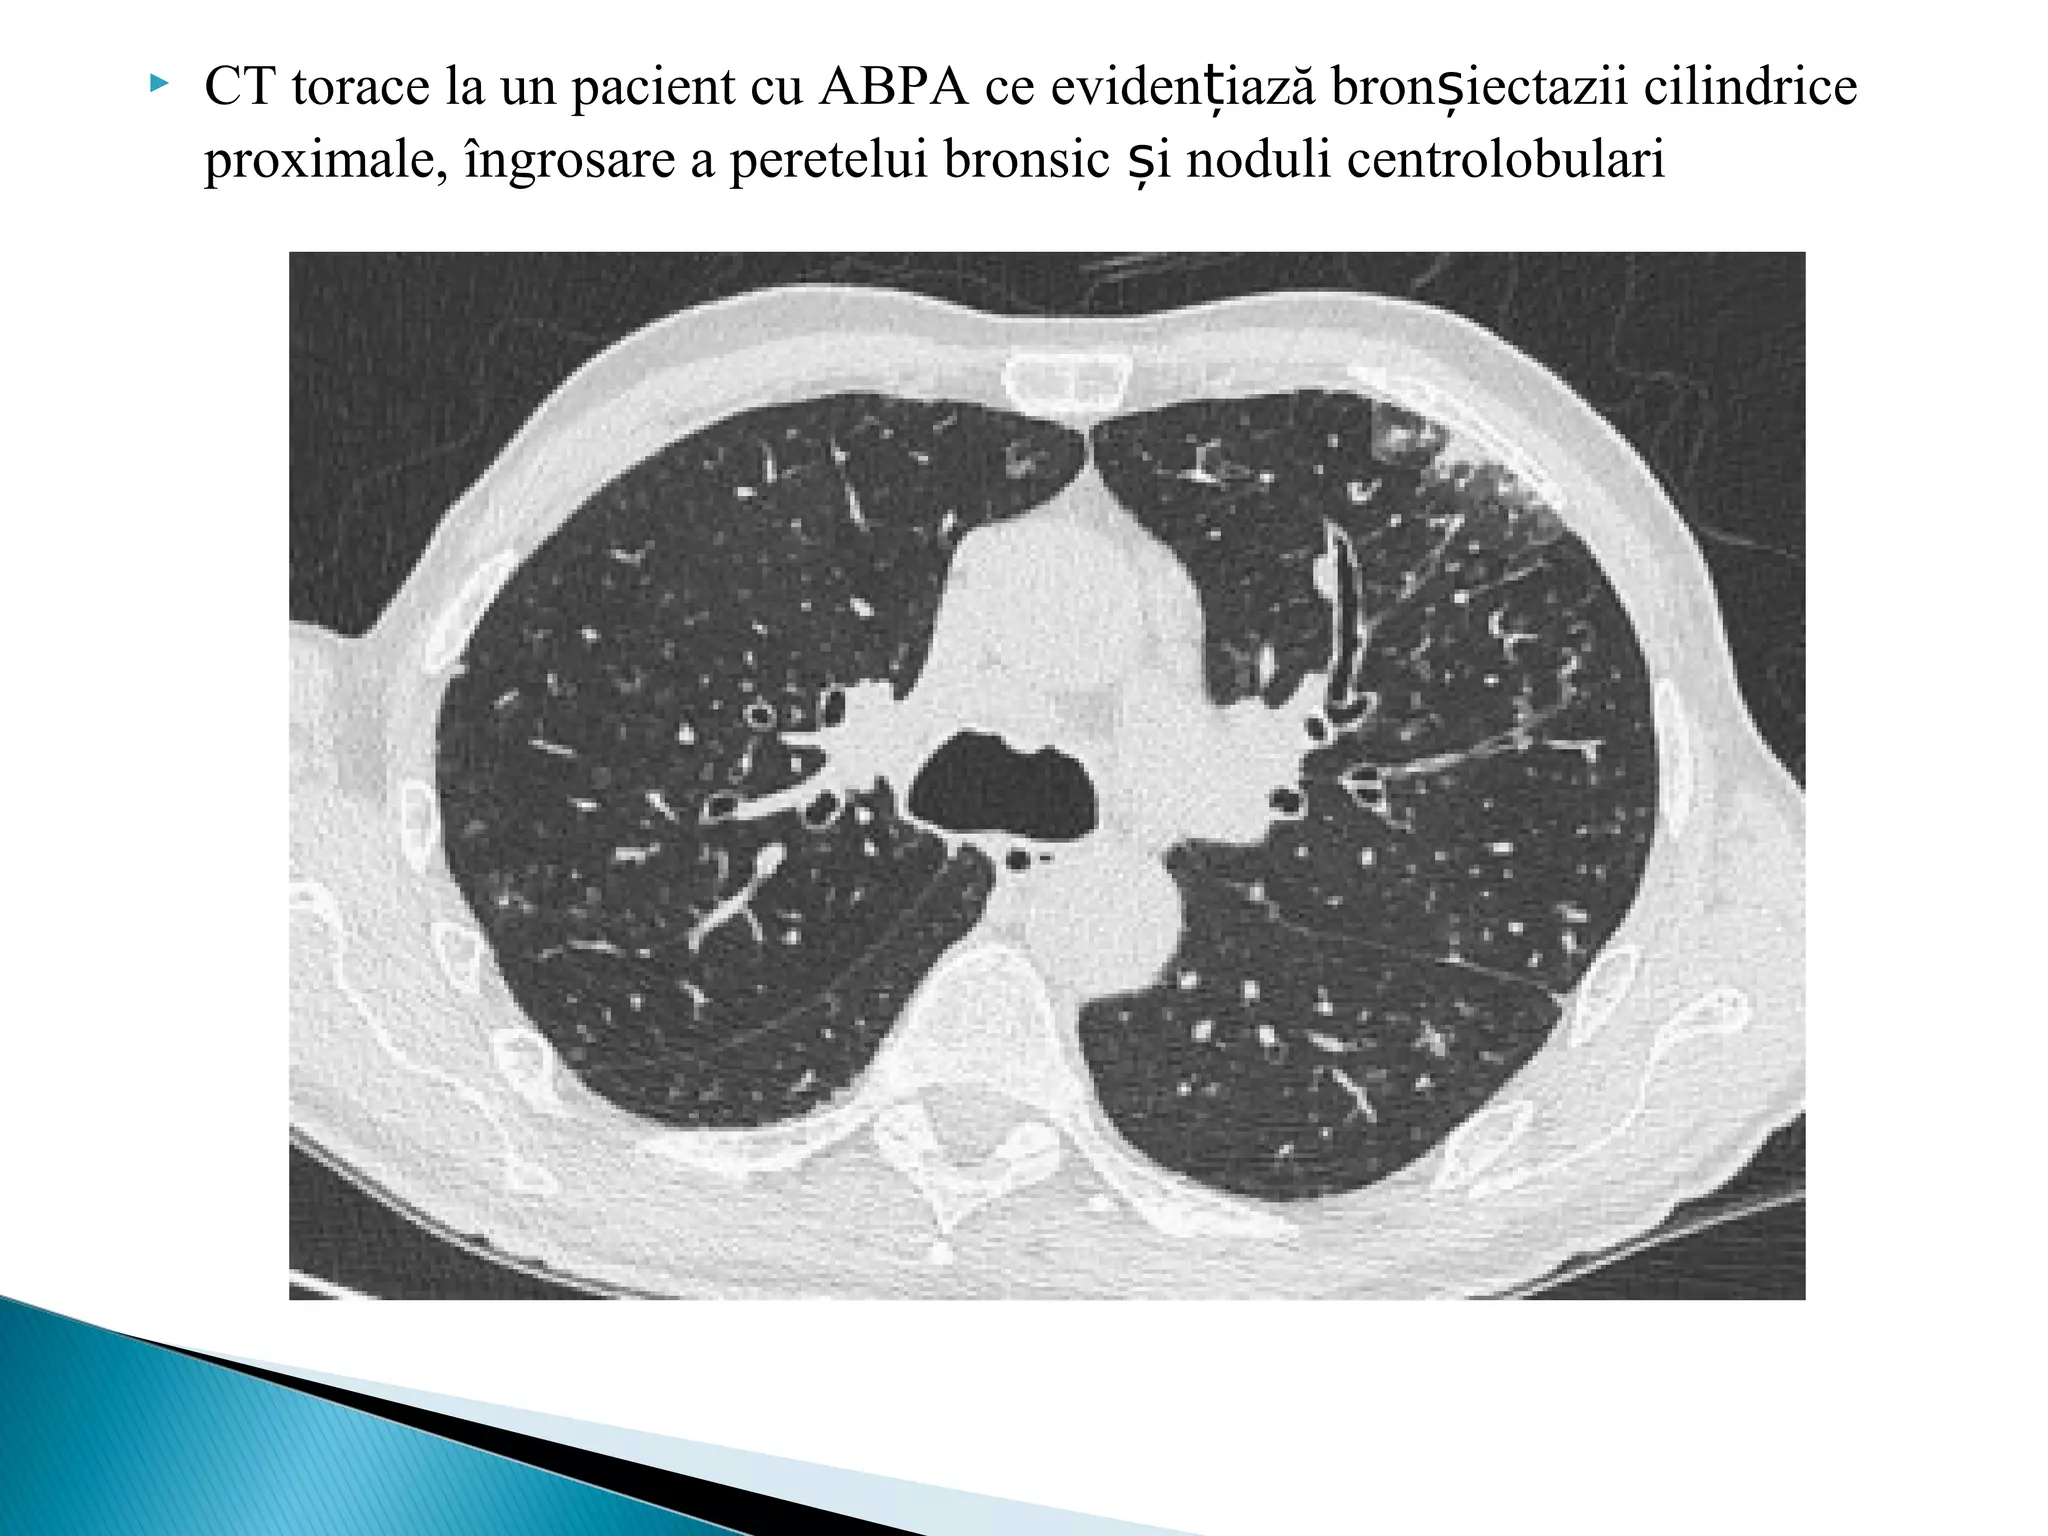

 CT torace la un pacient cu ABPA ce eviden iazăț bronșiectazii cilindrice

proximale, îngrosare a peretelui bronsic iș noduli centrolobulari

Aspectele imagistice suntreprezentate de : bronșiectazii - cele mai frecvente semne ce sugereaza ABPA la astmatici pereti bronsici ingrosati dopuri mucoase (aspect în deget de manusă- corespunde impactarii mucusului bronsic de la hil la periferie imagini cu aspect de „sticlă mată”

 CT toracela un pacient cu ABPA ce eviden iazăț bronșiectazii cilindrice proximale, îngrosare a peretelui bronsic iș noduli centrolobulari